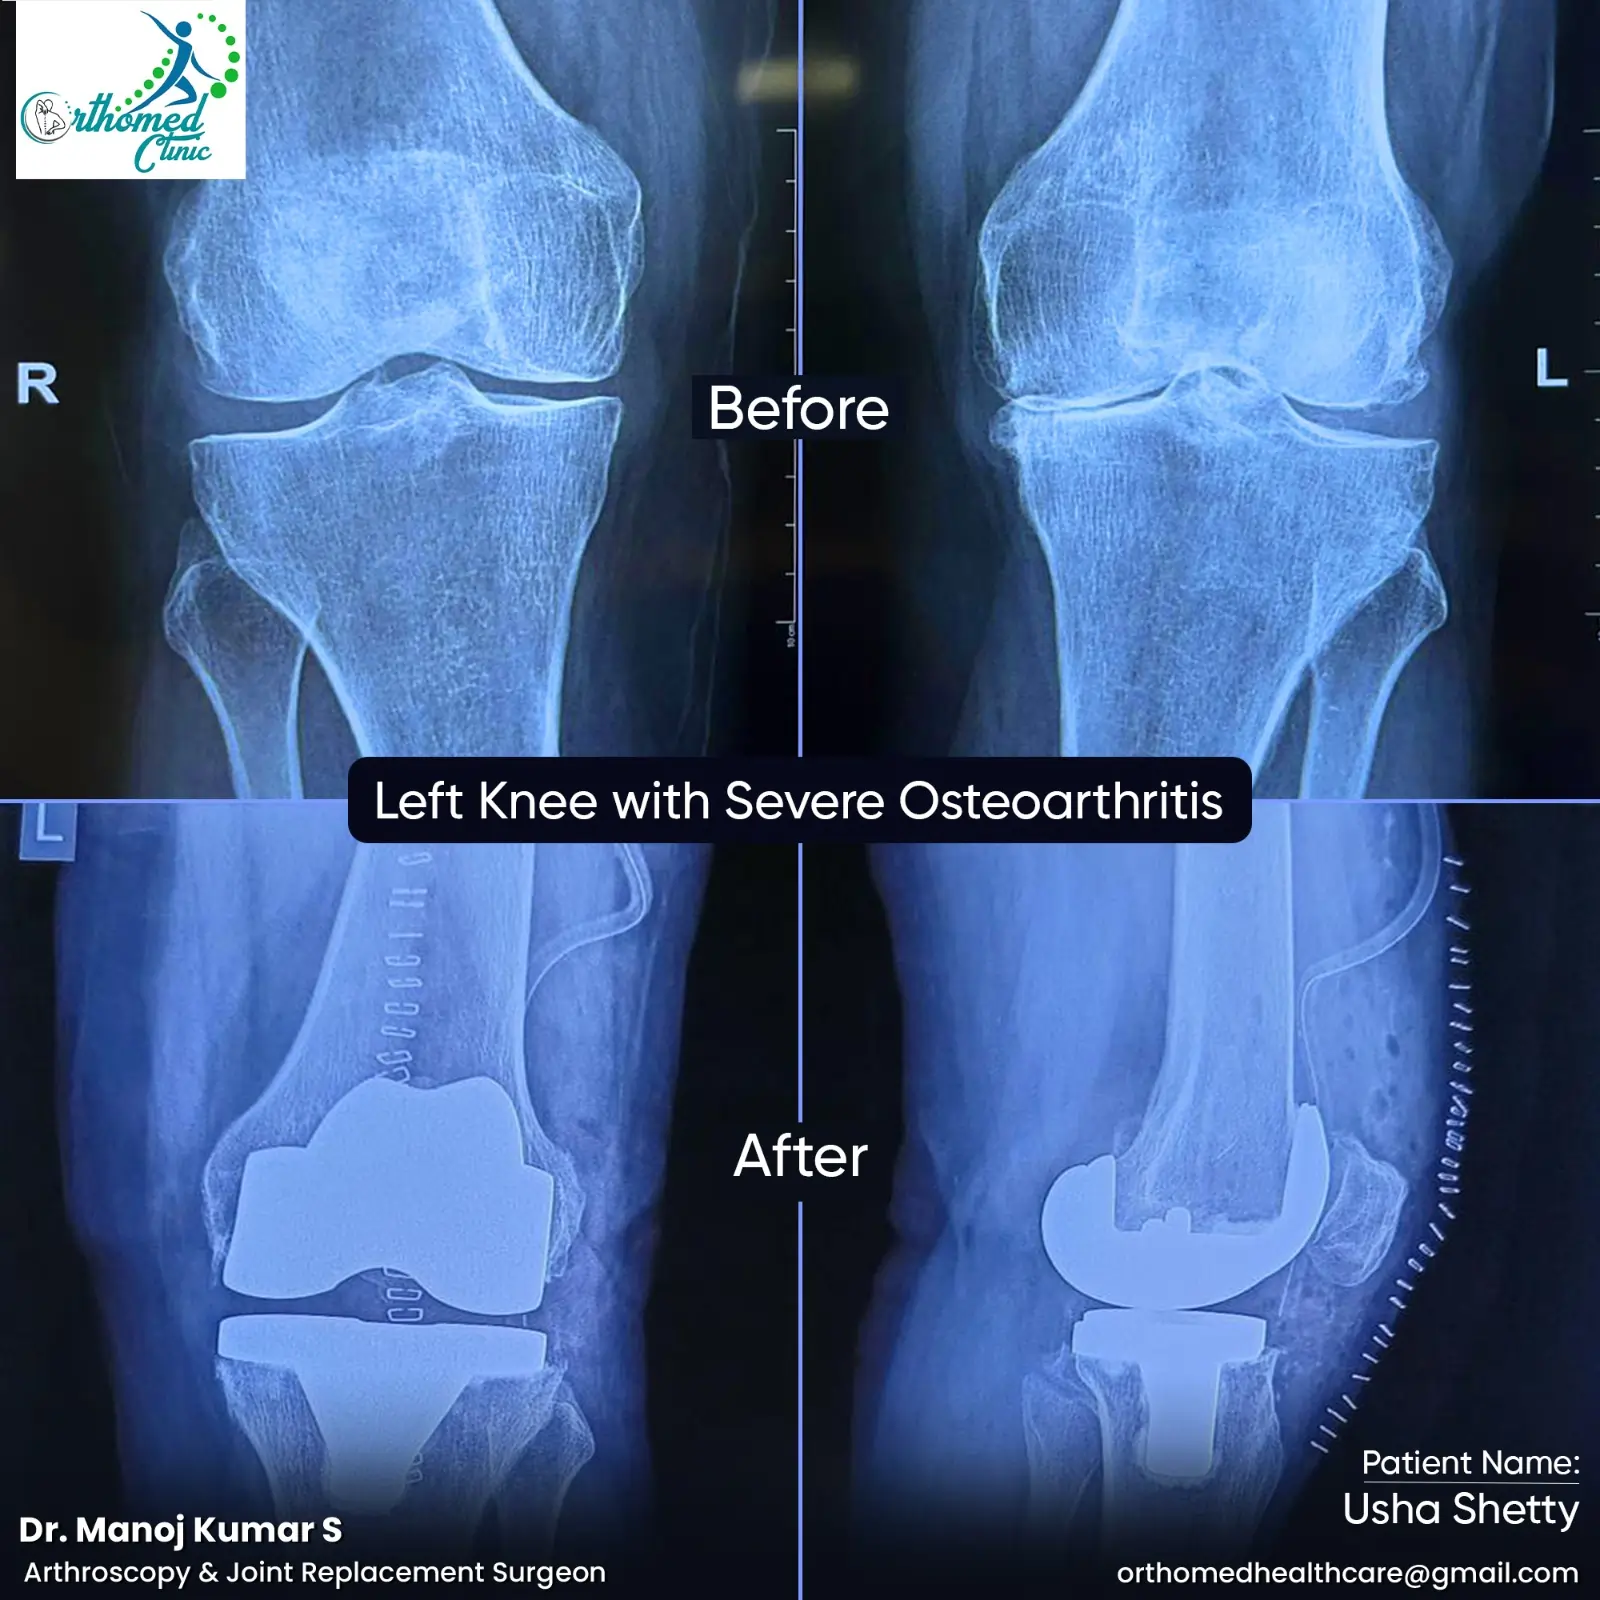

• Joint Replacement (Hip & Knee joint)

Surgical Images